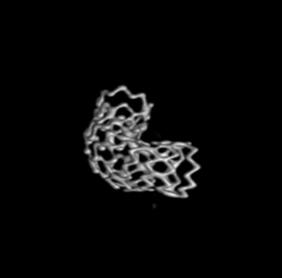

3D重建图示支架贴壁良好。